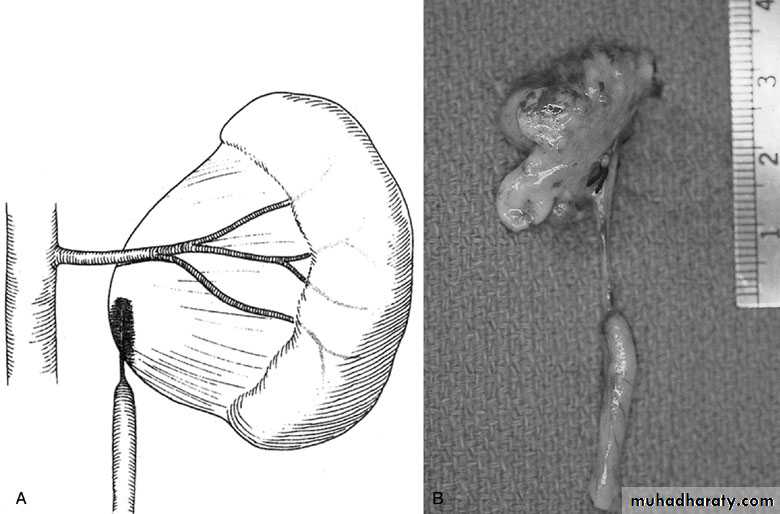

Treatment:

Medical: control infection and pain.

Surgical:

Indications for surgery:

1-progressive hydronephrosis.

2- UTI, and symptomatic patients.

3- Severe hydronephrotic non functioning kidney.

Treatment

SURGICAL REPAIR including open surgical techniques, laparoscopic, & endoscopic approaches

Open & laparoscopic surgical techniques Anderson-Hynes dismembered pyeloplasty:

excision of the pathologic UPJ & appropriate

reanastamosis or flap technique or flap

operation

Nephrectomy

for non functioning kidney